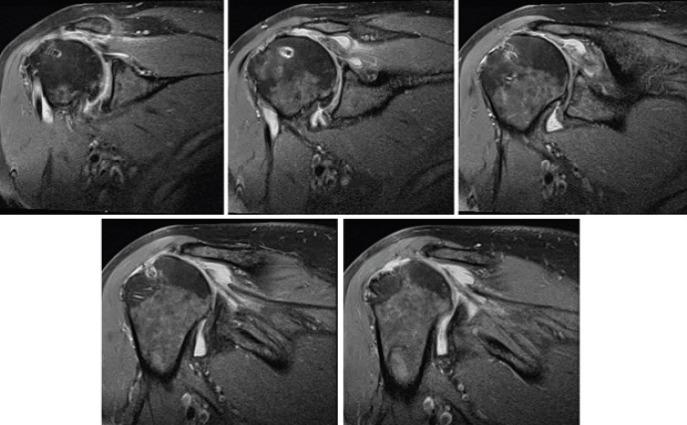

We report the case of a 64-year-old active male who had previously underwent a subacromial balloon placement in his right shoulder and an arthroscopic rotator cuff repair procedure on his left shoulder. He later presented with persistent pain and disability in his left shoulder and opted to undergo a second subacromial balloon placement on his left side. To the best of our knowledge, this is the first case of bilateral subacromial balloon placement procedure in the literature.

我们报告了一例64岁的活跃男性病例,该患者先前在其右肩进行了肩峰下气囊置入术,并在其左肩进行了关节镜下肩袖修复手术。他后来出现左肩持续疼痛和功能障碍,并选择在左侧进行第二次肩峰下气囊置入术。据我们所知,这是文献中首例双侧肩峰下气囊置入手术的病例。